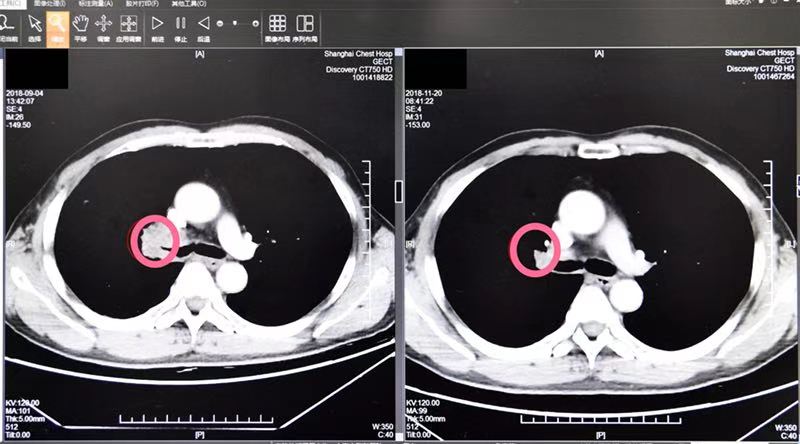

在肿瘤科陆舜主任的带领下,由肿瘤科(内科、外科)、放射科、病理科等组成的团队,经过多次研讨和会诊,在一个月内,通过免疫治疗方法,蒋老伯肺里的肿瘤从原来的4.2公分缩小到了2.8公分,整整减少了30%!手术指征有了!

免疫治疗后,肿瘤减小了整整30%

30天的治疗后,专家们欣喜地发现老人的肿瘤组织明显缩小,肺动脉侵犯减少,虽然手术难度还是很大,但各项指征都已经符合标准。